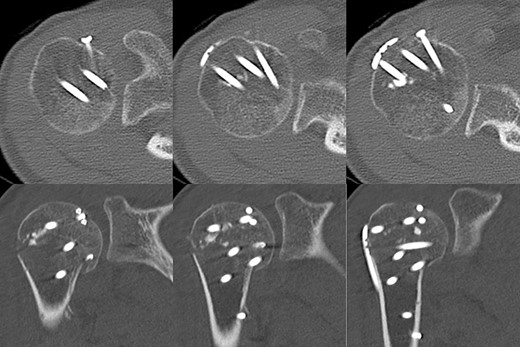

A 39-year-old man was transported via ambulance after being hit by a car. The radiographs revealed a one-part proximal humeral fracture with displacement at the surgical neck (Fig. 1). However, computed tomography (CT) revealed humeral head impression fracture and lesser tuberosity fracture in addition to a surgical neck fracture (Fig. 2). In addition, 3D-CT revealed that the collapse occupied approximately 20% of the articular surface with no glenoid defect (Fig. 3). Therefore, we first performed arthroscopic-assisted reduction and internal fixation of the humeral head impression fracture, followed by open reduction and internal fixation (ORIF) of the proximal humeral fracture.

3D-CT scan showing approximately 20% of articular surface of the right proximal and no glenoid defect, indicating no posterior shoulder dislocation.